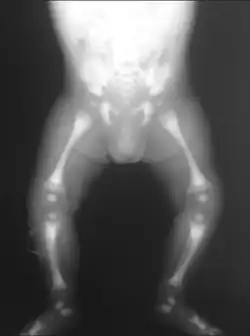

X-ray of the pelvis of a patient with osteopetrosis, adult onset form (Albers-Schönberg disease). Note the dense appearance. | |